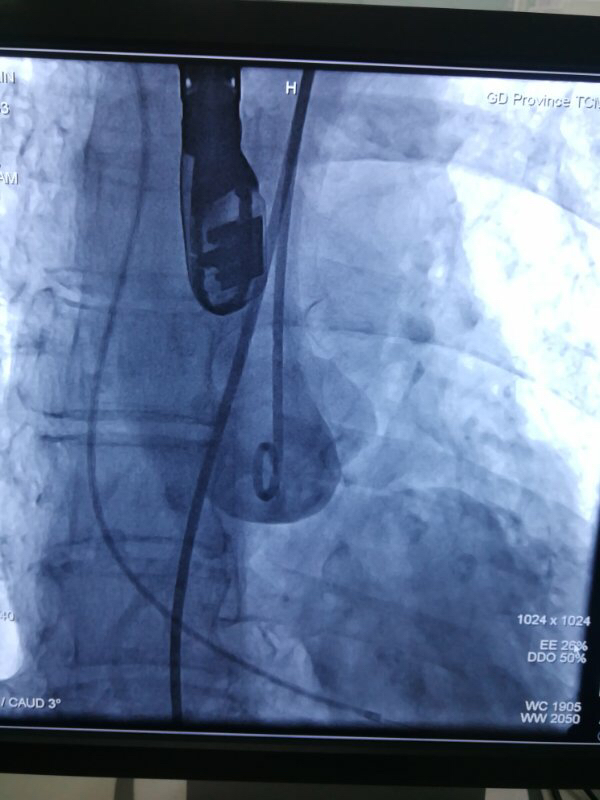

图片说明:造影评估主动脉根部结构。

术中,在TAVI心脏手术团队的协作下,首先在患者心尖部位开一小孔,然后操控一根细长的输送鞘,将人工生物心脏瓣膜送入患者心腔。在造影屏幕监视下,新瓣膜被准确定位和放置于病变主动脉瓣位置。原来的心脏泵血“阀门”因关不紧“漏水”,新瓣膜“安装”完毕后,就像一扇运行良好的新“阀门”,一张一合地开始工作了。